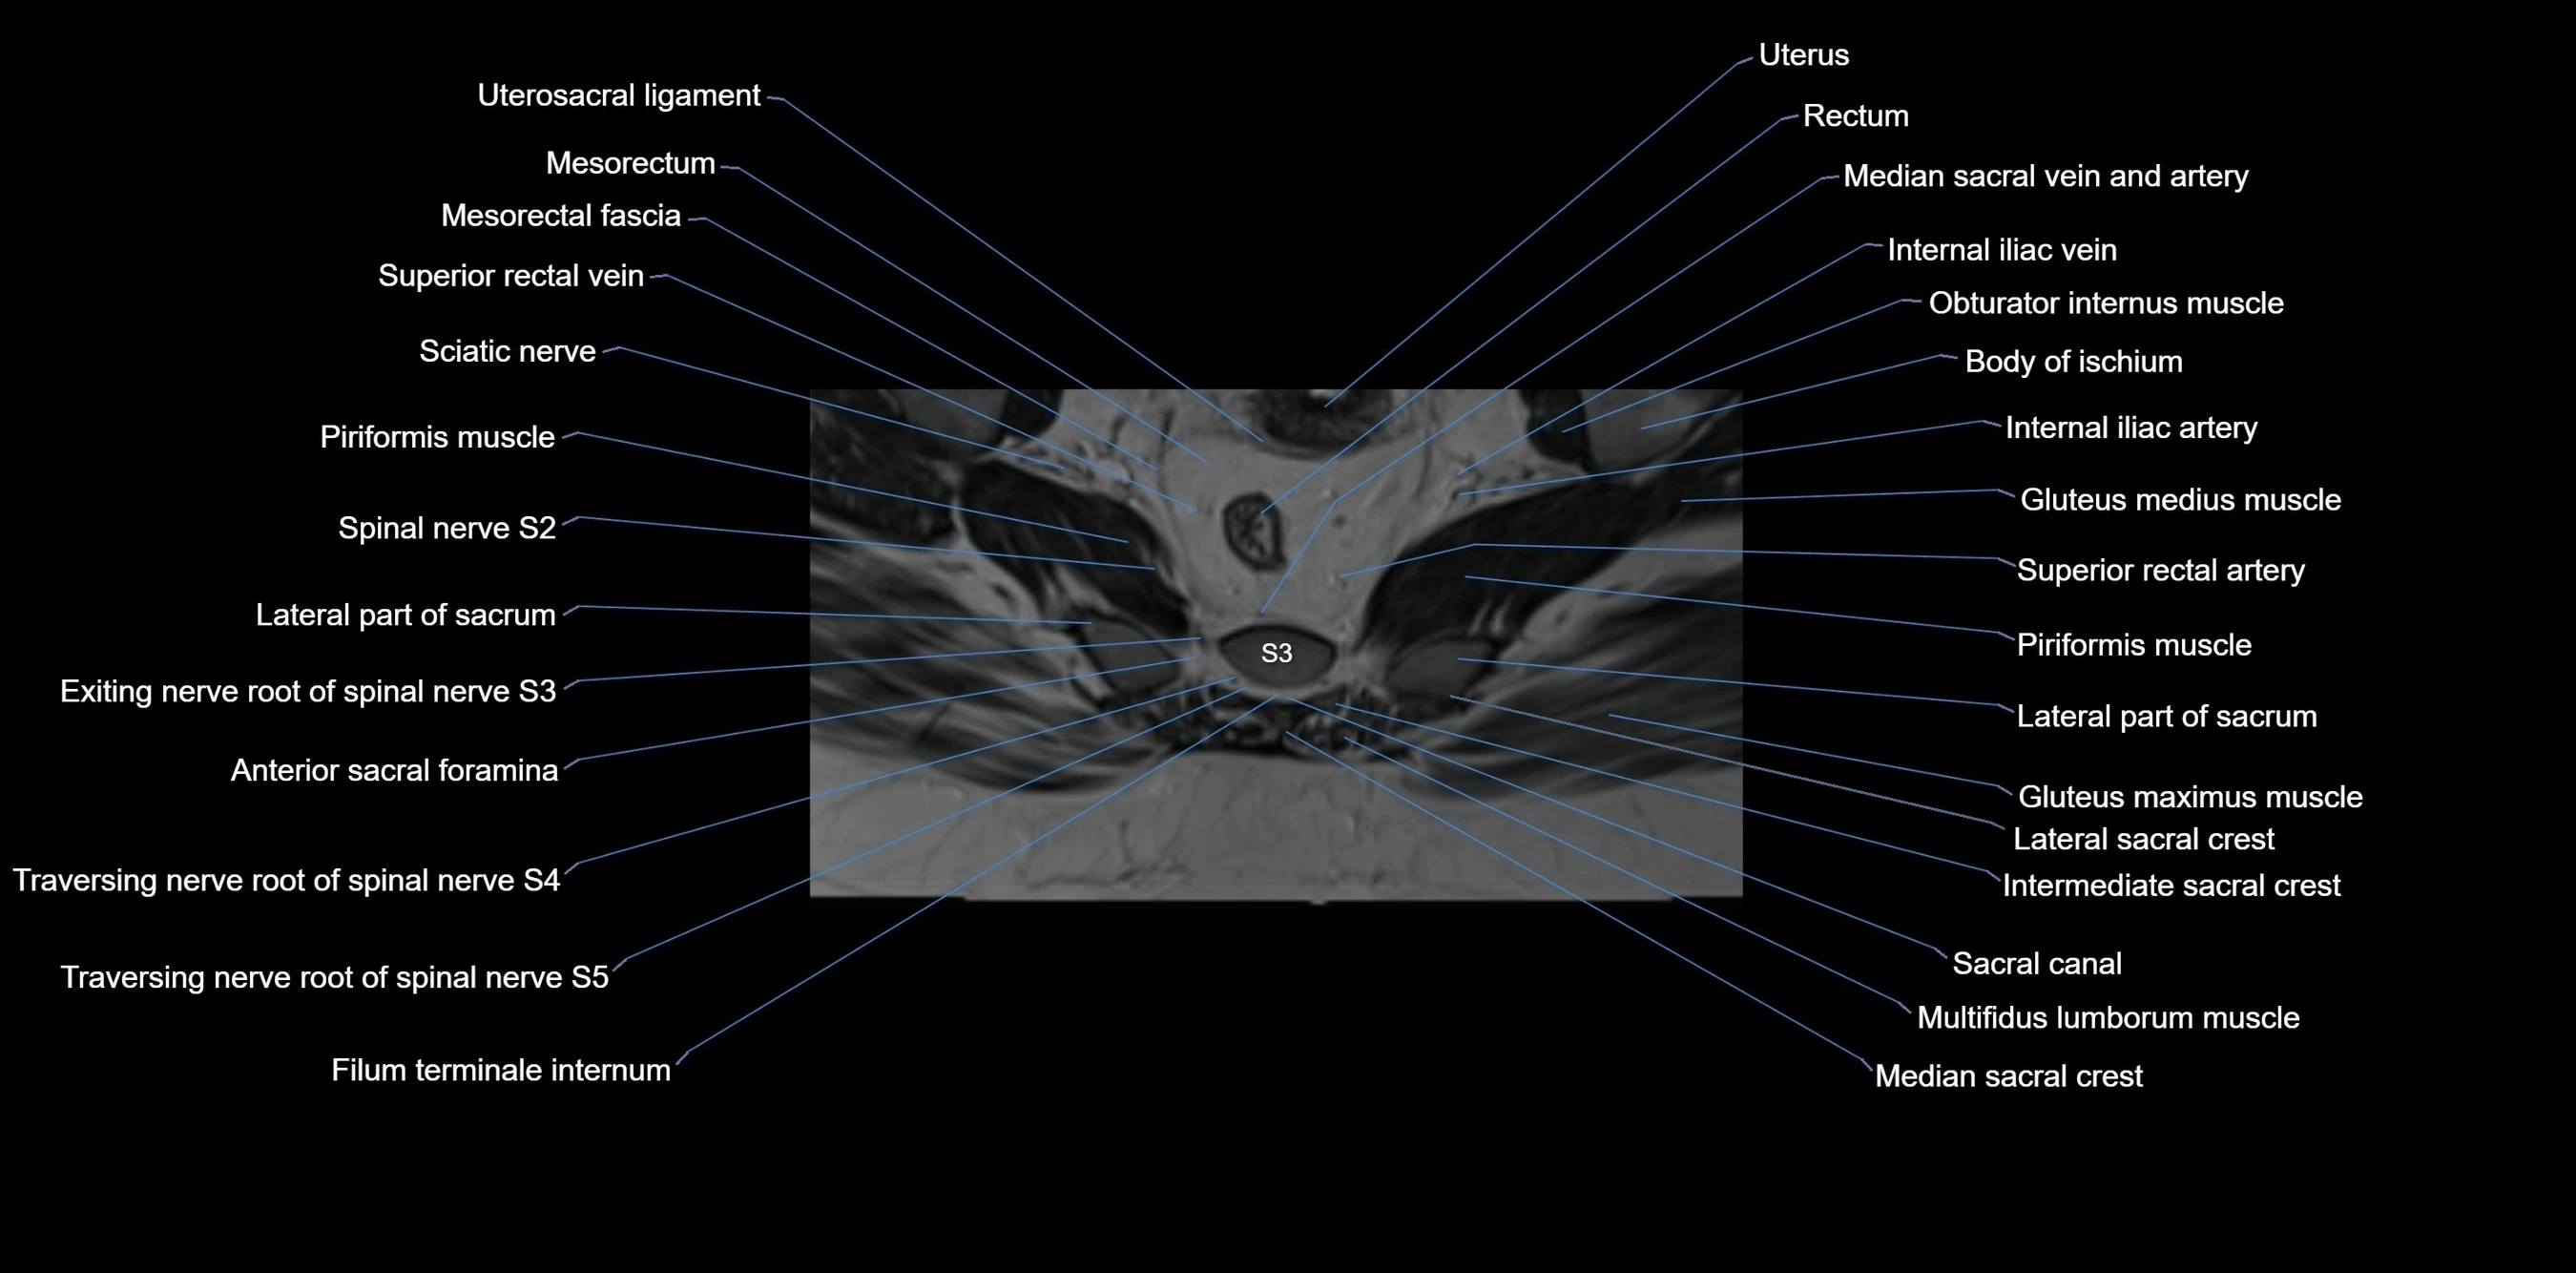

MRI image

image